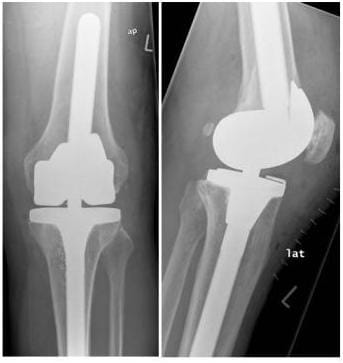

Bei einer Arthrose, die das gesamte Knie betrifft, wird diese Prothese verwendet. Optional kann auch die Rückfläche der Kniescheibe ersetzt werden. Eine wesentliche Voraussetzung für diesen Prothesentyp ist eine noch ausreichende Stabilität des Gelenkes.

Röntgenbild Bikondylärer Oberflächenersatz

Kompletter Oberflächenersatz mit einer totalen Knieendoprothese: Mit diesem Prothesentyp können die meisten Gonarthrosen behandelt werden. Voraussetzung ist eine ausreichend stabile Bandführung des Kniegelenkes. (Bilder: Orthopädie)